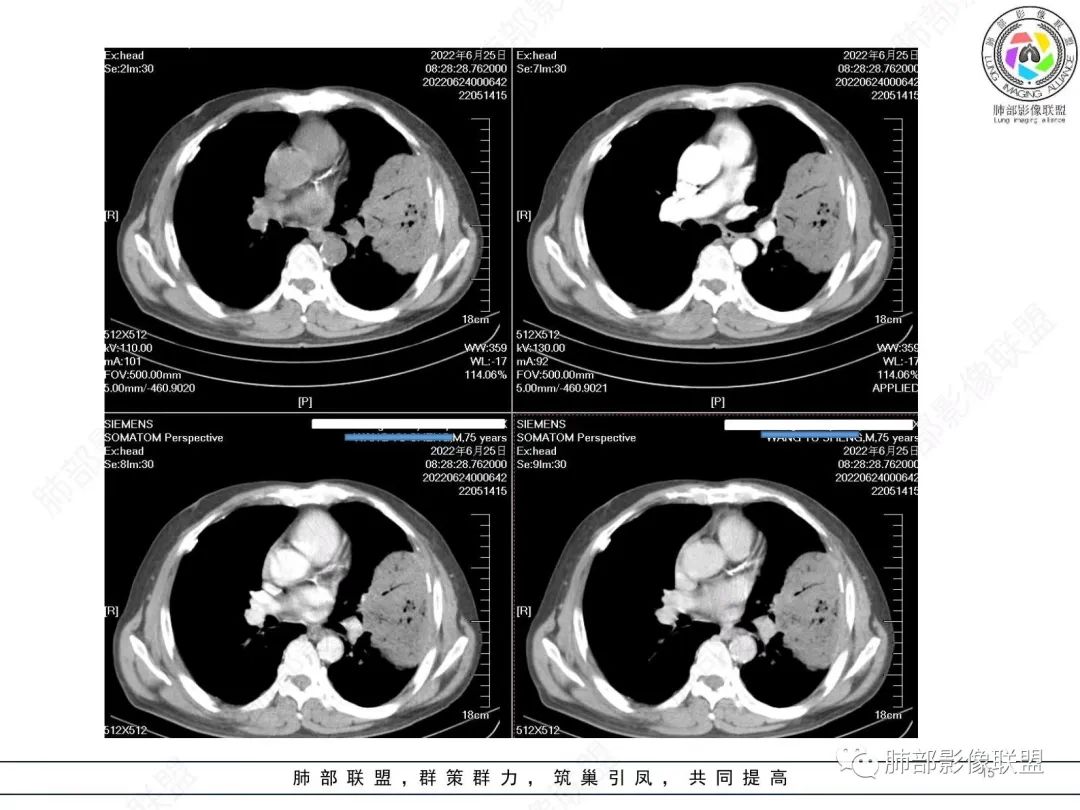

我要修正一下观点了:仔细看了视频,肿块占位效应明显,对周围血管,支气管有推挤,增强后强化不明显,NSE增高,半年体重下降25公斤,虽然有内部支气管扩张,血管漂浮,边界清楚支持淋巴瘤,但强化太低,膨隆,占位推挤太明显(淋巴瘤一般没有这么明显的占位效应),胸膜关系有载桩,恶病质明显(乏力,半年体重下降了25公斤),NSE也明显增高,就不支持淋巴瘤了。还是考虑外朝内的恶性肿瘤,间质来源的肉瘤伴有神经内分泌分化或者大神泌。

不支持淋巴瘤的有四点:1、对周围血管支气管推挤明显。2、胸膜有栽桩,3、强化太弱(淋巴瘤一般还是中度以上甚至高度强化多见),4、NSE升高明显,体重下降太明显。

我再建一下血管。支气管进入,但是近端推移,堵塞

大肿块,边缘光滑,深分叶

近端支气管堵塞、推移为主

部分类似于脐凹征

内部支气管扩张

肺动脉推移为主,边缘部分进入